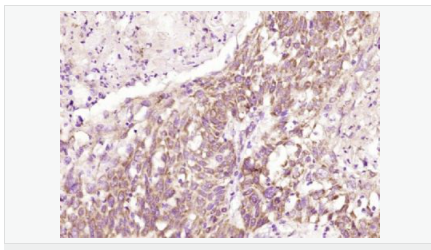

| 產(chǎn)品應(yīng)用 | WB=1:500-2000 ELISA=1:5000-10000 IHC-P=1:100-500 IHC-F=1:100-500 ICC=1:100-500 IF=1:100-500 (石蠟切片需做抗原修復(fù)) not yet tested in other applications. optimal dilutions/concentrations should be determined by the end user. |

| 產(chǎn)品介紹 | This gene encodes a type I transmembrane protein and is a tumor-specific endothelial marker that has been implicated in colorectal cancer. The encoded protein has been shown to also be a docking protein or receptor for Bacillus anthracis toxin, the causative agent of the disease, anthrax. The binding of the protective antigen (PA) component, of the tripartite anthrax toxin, to this receptor protein mediates delivery of toxin components to the cytosol of cells. Once inside the cell, the other two components of anthrax toxin, edema factor (EF) and lethal factor (LF) disrupt normal cellular processes. Three alternatively spliced variants that encode different protein isoforms have been described. [provided by RefSeq, Oct 2008] Function: Plays a role in cell attachment and migration. Interacts with extracellular matrix proteins and with the actin cytoskeleton. Mediates adhesion of cells to type 1 collagen and gelatin, reorganization of the actin cytoskeleton and promotes cell spreading. Plays a role in the angiogenic response of cultured umbilical vein endothelial cells. Subunit: Interacts with gelatin and type 1 collagen. Interacts with the actin cytoskeleton. Binds to the protective antigen (PA) of Bacillus anthracis. Binding does not occur in the presence of calcium. Subcellular Location: Cell membrane; Single-pass type I membrane protein. Cell projection, lamellipodium membrane; Single-pass type I membrane protein. Cell projection, filopodium membrane; Single-pass type I membrane protein. Note=At the membrane of lamellipodia and at the tip of actin-enriched filopodia. Colocalizes with actin at the base of lamellipodia. Tissue Specificity: Detected in umbilical vein endothelial cells (at protein level). Highly expressed in tumor endothelial cells. DISEASE: Defects in ANTXR1 are associated with susceptibility to hemangioma capillary infantile (HCI) [MIM:602089]. HCI are benign, highly proliferative lesions involving aberrant localized growth of capillary endothelium. They are the most common tumor of infancy, occurring in up to 10% of all births. Hemangiomas tend to appear shortly after birth and show rapid neonatal growth for up to 12 months characterized by endothelial hypercellularity and increased numbers of mast cells. This phase is followed by slow involution at a rate of about 10% per year and replacement by fibrofatty stroma Similarity: Belongs to the ATR family. Contains 1 VWFA domain. SWISS: Q9H6X2 Gene ID: 84168 Database links: Entrez Gene: 84168 Human Entrez Gene: 69538 Mouse Omim: 606410 Human SwissProt: Q9H6X2 Human SwissProt: Q9CZ52 Mouse Unigene: 165859 Human Unigene: 232525 Mouse Unigene: 41192 Rat Important Note: This product as supplied is intended for research use only, not for use in human, therapeutic or diagnostic applications. |